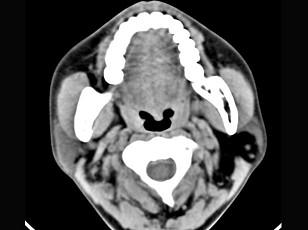

问题 男性38岁,左侧腮腺渐进性肿大一年,无压痛,CT扫描如图所示,请选择正确的描述和结论 ( )

选项 A、考虑为脂肪瘤 B、考虑为血管瘤 C、肿块边缘清楚,未见邻近结构受侵 D、考虑为囊肿 E、左侧腮腺区见低密度肿块,CT值约为-200Hu

答案 ACE